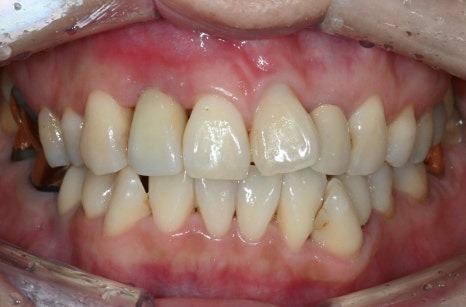

만 90세의 어르신께서

위 턱 전체 치아가 없어서

식사가 힘들다며 내원하셨습니다.

아래 턱에는 치아가 남아있거나

임플란트로 회복된 부분이 있었지만,

위 턱은 앞니는 뿌리만 남았고

다른 치과에서 어금니 임플란트 실패까지

겪으시며 마음 고생이 많이

심한 상황이셨습니다.